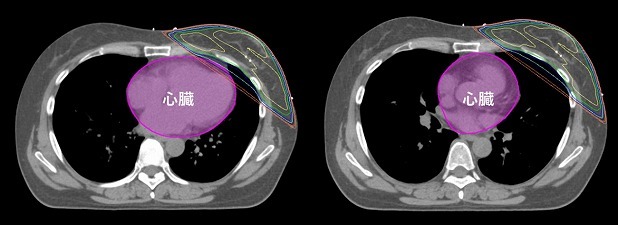

また、左乳がんの場合、通常の照射法では左乳房に近接する心臓に悪影響を与えるおそれがあります。当院では、心臓への影響を避けるため深吸気息止め照射という照射法を用いています。

乳がんで乳房温存手術後。再発を防ぐため同側の乳房全体に照射。

左乳がんの場合、従来の照射法(左図)では近接する心臓がわずかだが照射される。

深吸気息止め照射法(右図)を用いると心臓が照射されなくなることが多い。